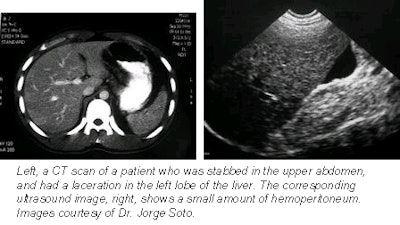

According to the results, the ultrasound exam demonstrated abnormalities in 43.8% of the patients. Of these 14 cases, 8 had free fluid at admission; the initial sonogram revealed an associated solid organ injury. In one instance, initial ultrasound did not detect a hepatic lesion, but the patient recovered with conservative treatment.

In the case of CT, the scan depicted intraperitoneal abnormalities in 65.6% of patients, including free peritoneal fluid and renal laceration. In 12 out of 21 patients, CT showed abnormalities that were not detected with ultrasound, the group reported.

Only one patient required laparotomy after the baseline ultrasound and the CT exam. Despite appropriate fluid replacement, the patient showed signs of peritoneal irritation. An extensive hepatic laceration and hemoperitoneum was found at laparotomy, the authors said.

In general, the group found that CT was more adept at demonstrating hepatic and renal injuries, while US was better for detecting increases in free fluid.